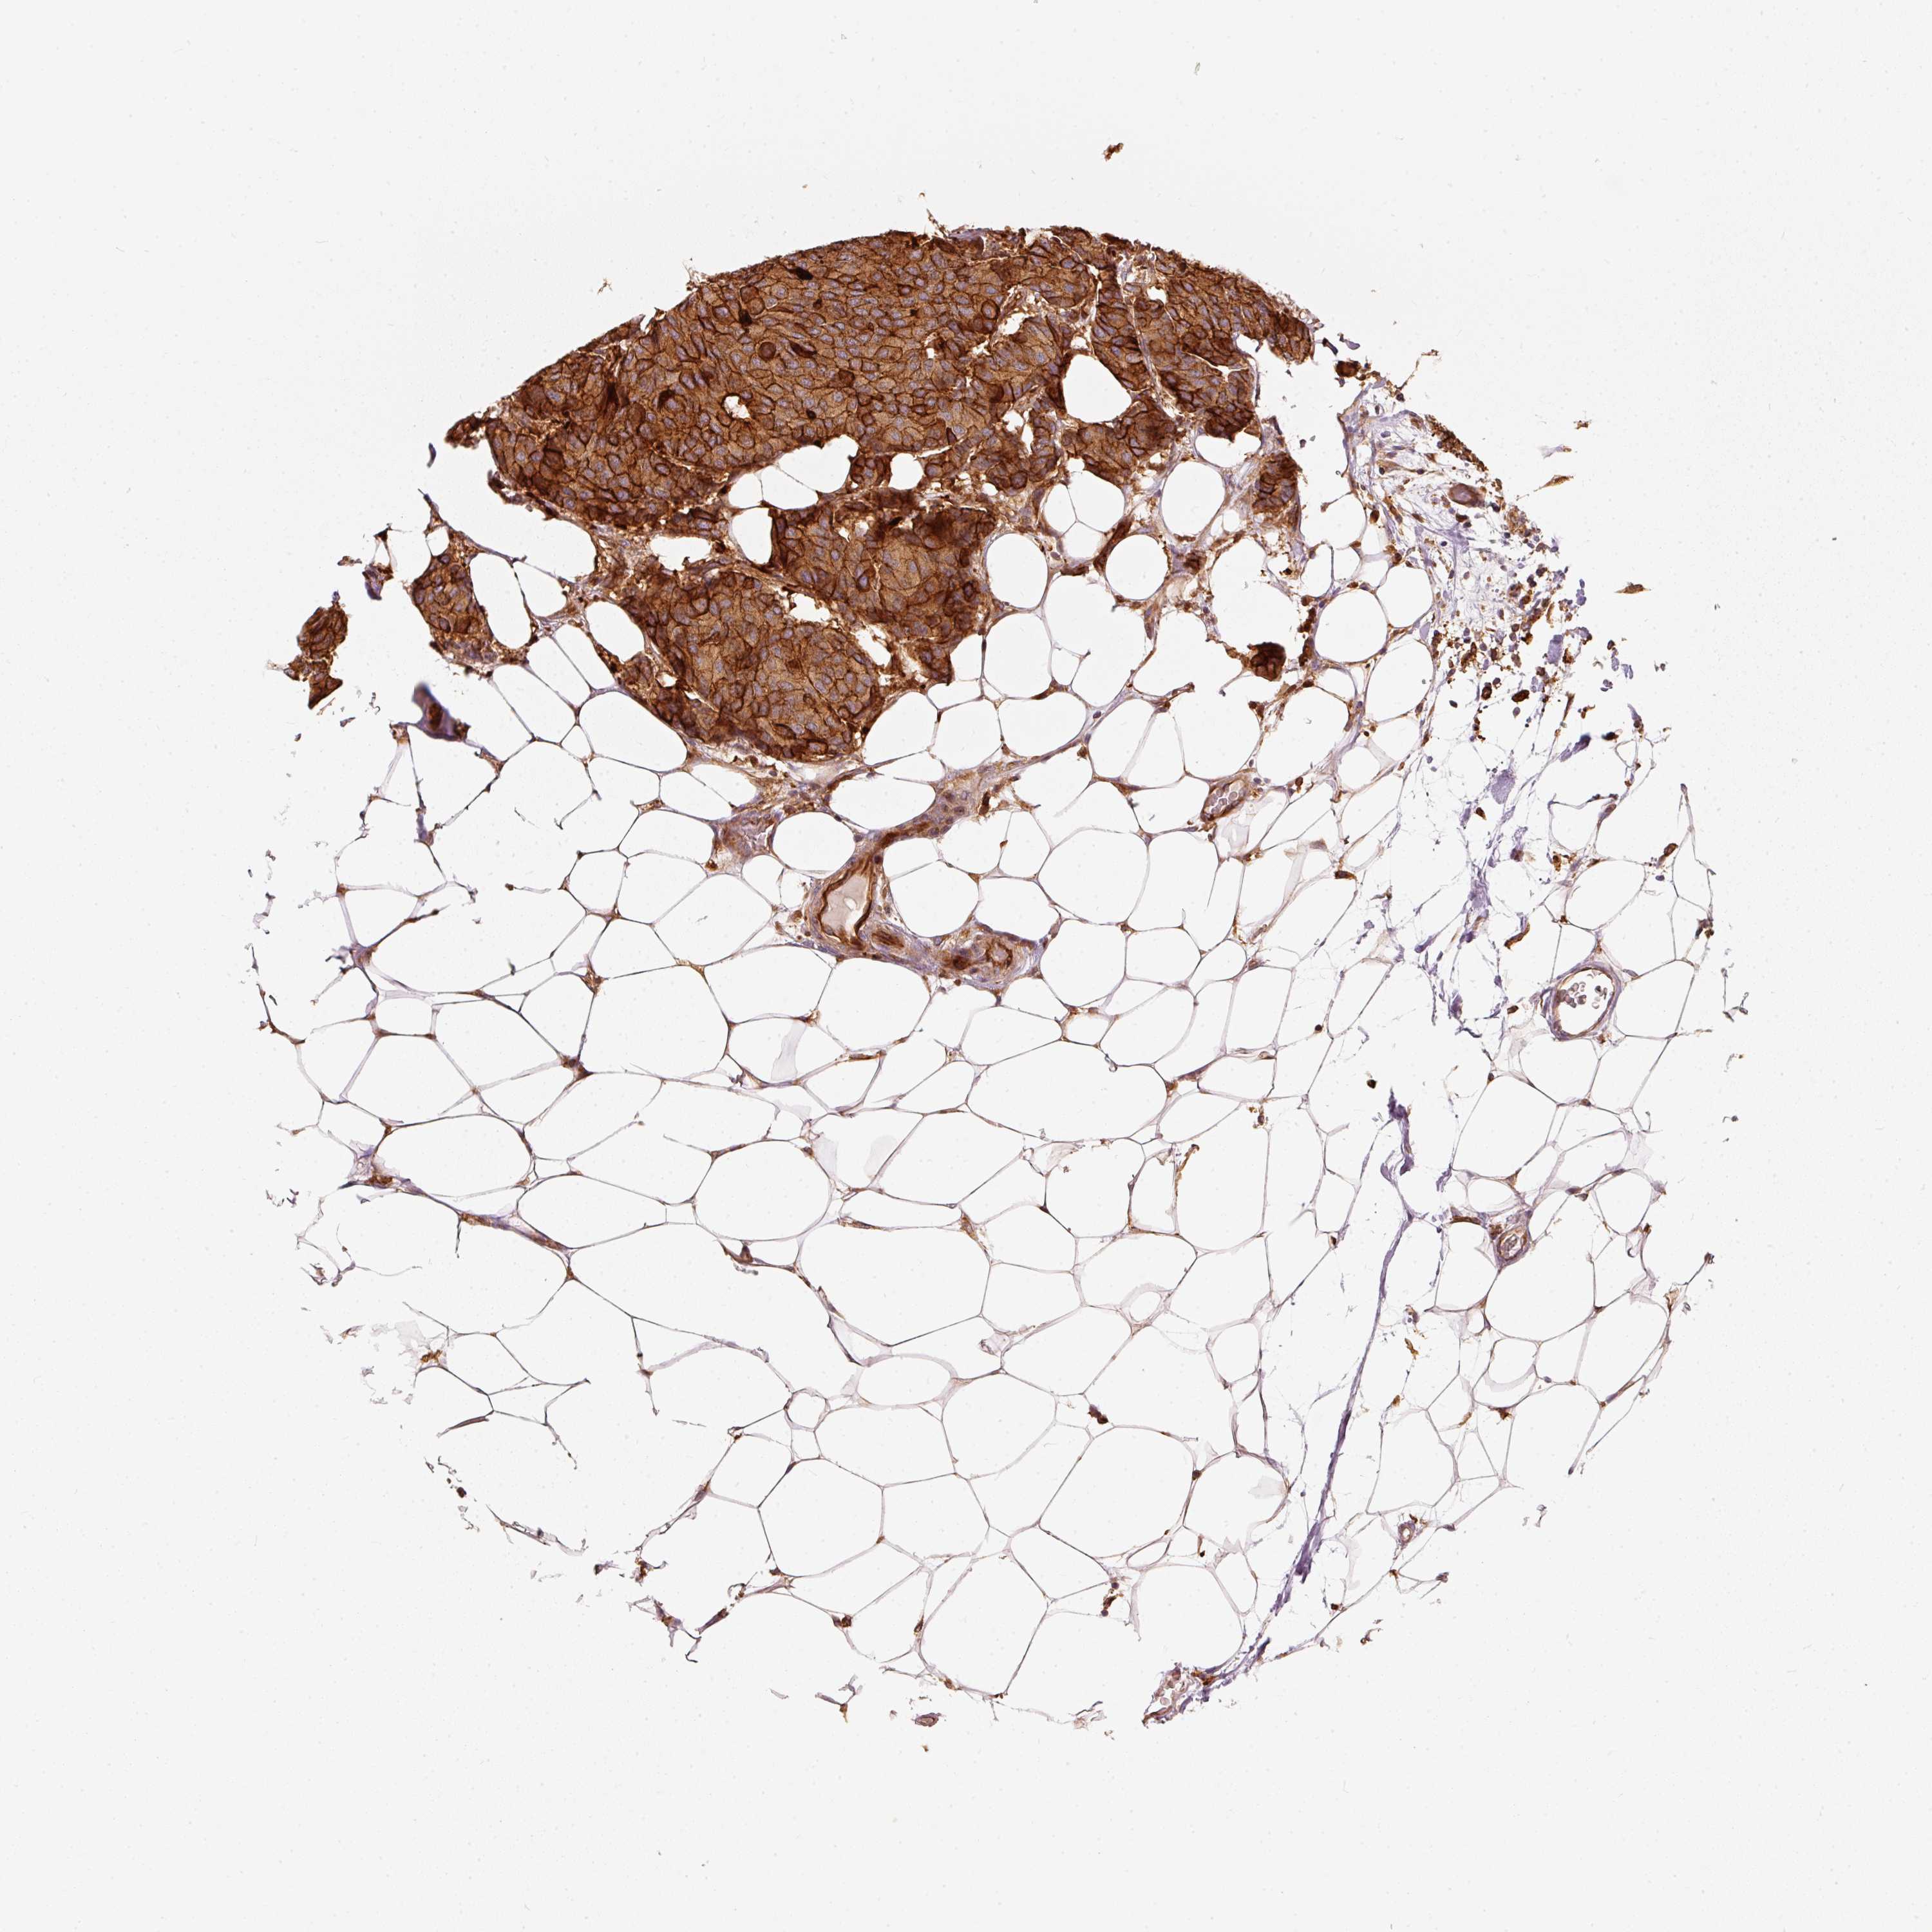

CANCER BREAST CANCER Show tissue menu

BRCA TCGA BRCA VALIDATION PROTEIN EXPRESSION